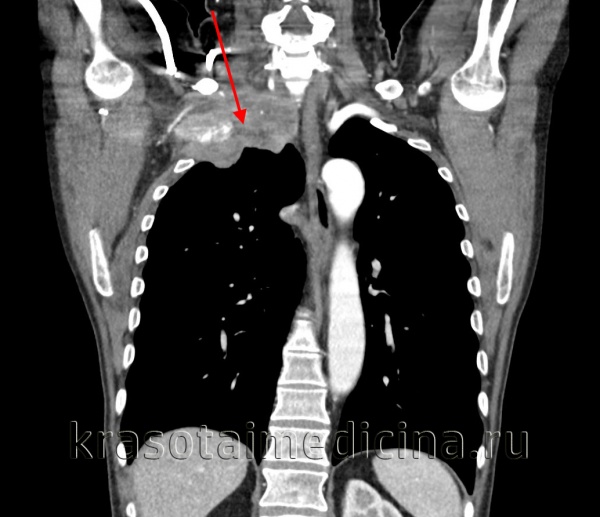

(а) Мужчина 68 лет с опухолью Панкоста и жалобами на боль в левом плечевом суставе в течение 6 месяцев.

При рентгенографии органов грудной клетки в ПП проекции определяется неравномерное утолщение верхушечной плевры слева без признаков вовлечения в процесс костной ткани.

Опухоль Панкоста при рентгенографии может визуализироваться плохо, как в данном случае.

(б) У этого же пациента при КТ с контрастным усилением в верхушке левого легкого выявляется мягкотканное объемное образование.

Левая подключичная артерия в опухолевый процесс не вовлечена, поскольку визуализируется четко. Прилежащие к опухоли ребра без признаков эрозии или деструкции. (а) У этого же пациента при МРТ на Т1ВИ в коронарной плоскости определяется частичная облитерация субплевральной жировой клетчатки в области верхушки левого легкого вследствие инвазии ее опухолью Панкоста.